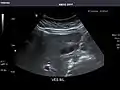

Aorta

Aorta: Visualized portions normal in caliber, 16 x 15 mm.

It can be used on the abdominal aorta to detect or exclude abdominal aortic aneurysm. For this purpose, the standard aortic measurement for abdominal aortic aneurysm is between the outer margins of the aortic wall.[4]